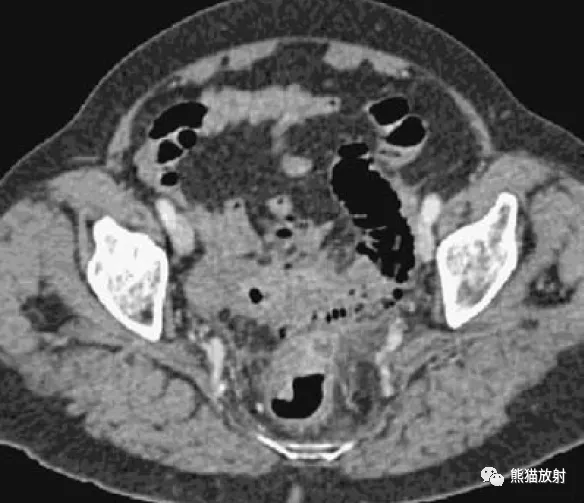

腹部影像图例结直肠篇